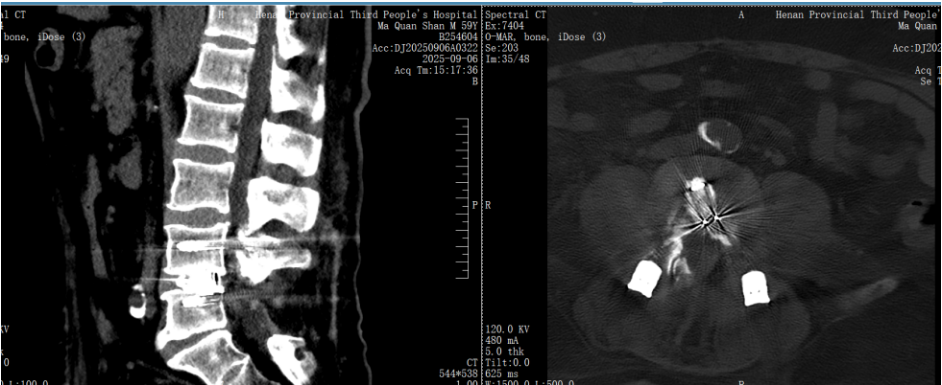

原来啊,在 20 年前他因腰椎问题接受了腰 5 骶 1 开放手术,但随后他的腰 4/5 节段出现不稳,腰部疼痛逐渐加剧,并伴有左下肢麻木、发凉,到了最近,他连日常行走站立都变得异常困难。

贺毅团队一致认为,传统开放手术风险过高,不适合马叔叔的情况。经过反复讨论,最终为他制定了内镜下腰 4/5 椎管减压+腰椎间盘切除+椎间植骨融合内固定术的微创手术方案。

手术过程很顺利,术后马叔叔腰部疼痛和左下肢麻木、发凉的症状明显缓解。